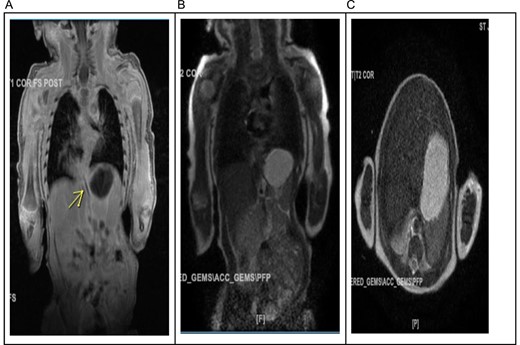

A 20-month female presented with her mother to the pediatric surgery office with a known history of pulmonary sequestration. Imaging at the time of birth revealed a 3.8 × 2.6 × 2.8 cm ovoid hazy opacity projecting in the right hemithorax in the expected location of the right lower lobe (Fig. 1). This was followed up with an MRI confirming a 2.9 × 2.6 cm segment of ELS arterial inflow identified from the celiac trunk (Fig. 2). No emergent surgeries were indicated at that time.

(A) The arterial supply to what appears to be a right lower lobe sequestration arises from the celiac trunk and there may be either a 2nd smaller artery arising more distally or a draining vein to the spleno-portal confluence. (B) The major venous drainage appears to extend to the right inferior pulmonary vein. (C) In the right lower lobe there is a 2.9 × 2.6 cm mass containing internal vascular architecture and suggestive of a sequestration.